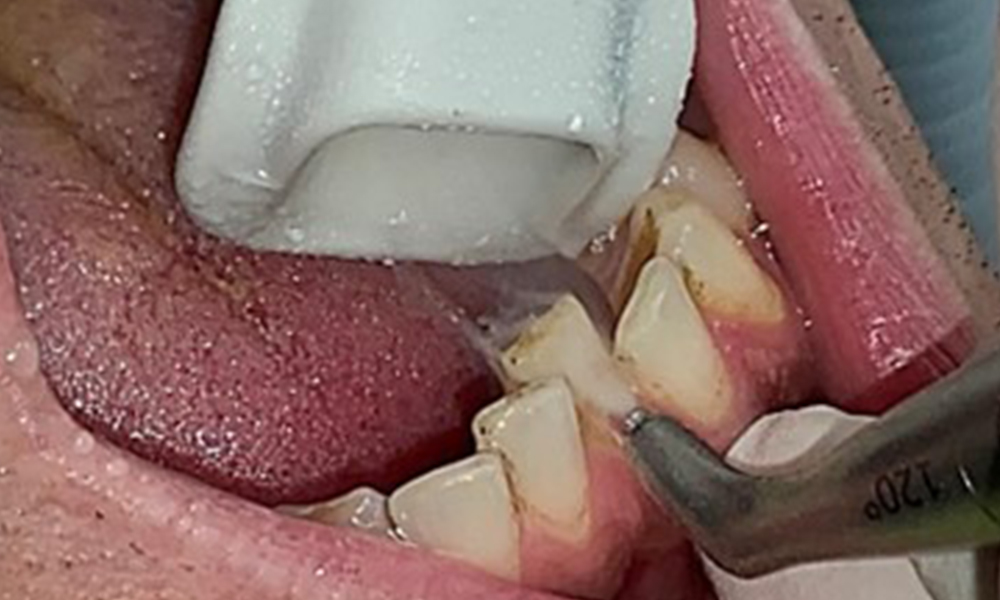

Due to the otherwise favourable general medical condition, the needs determined during the intraoral examination will be decisive for their treatment. It will be essential to periodically determine the probing depths. Gingival bleeding decreases in smokers, which is why the clinical diagnosis of periodontitis can only be made by probing (Fig. 7). Placing exclusive focus on the determination of bleeding indices may obscure existing periodontitis or gingivitis. (5)

Pocket probing (BOP) with depiction of tooth 36 lingual

Fig. 7 Pocket probing (BOP) with depiction of tooth 36 lingual, © Dr R. Krapf